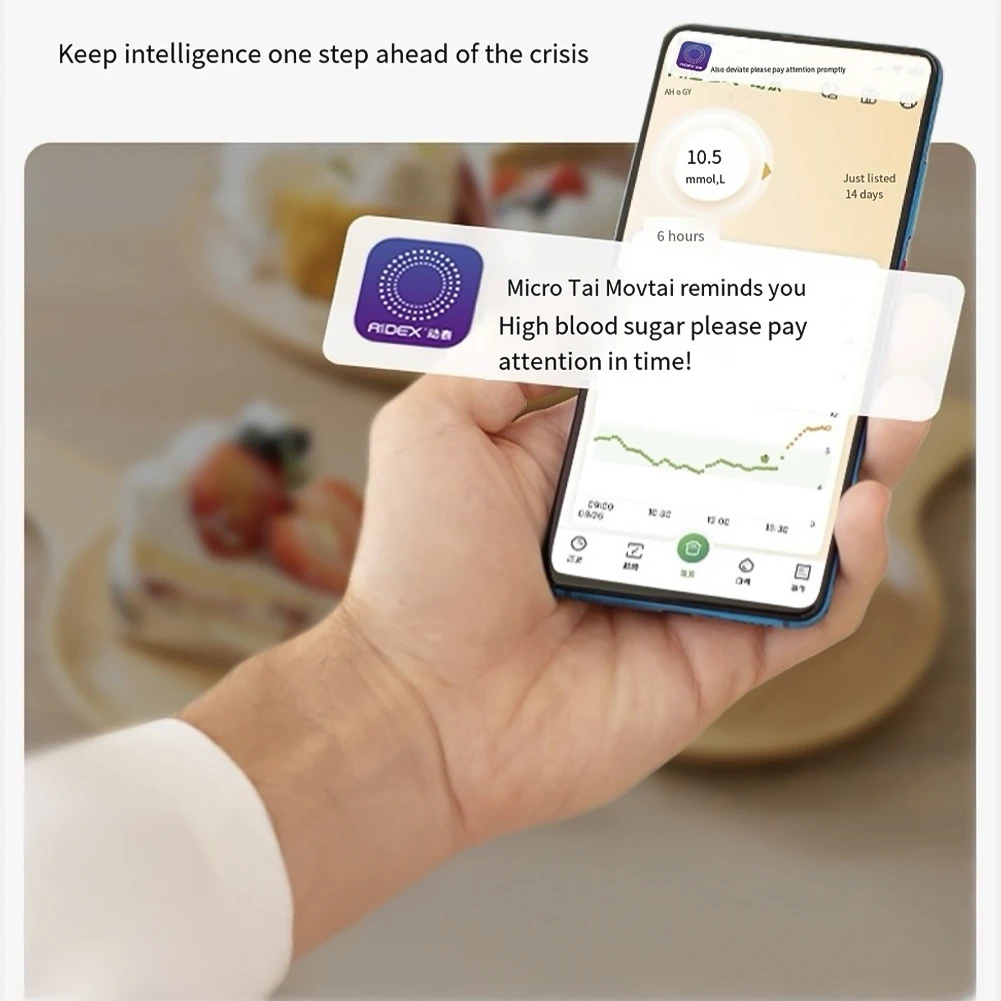

Battery Included: Yes

Brand Name: NoEnName_Null

Certification: CE

Choice: yes

Display Type: DIGITAL

Hign-concerned Chemical: None

Origin: Mainland China

semi_Choice: yes